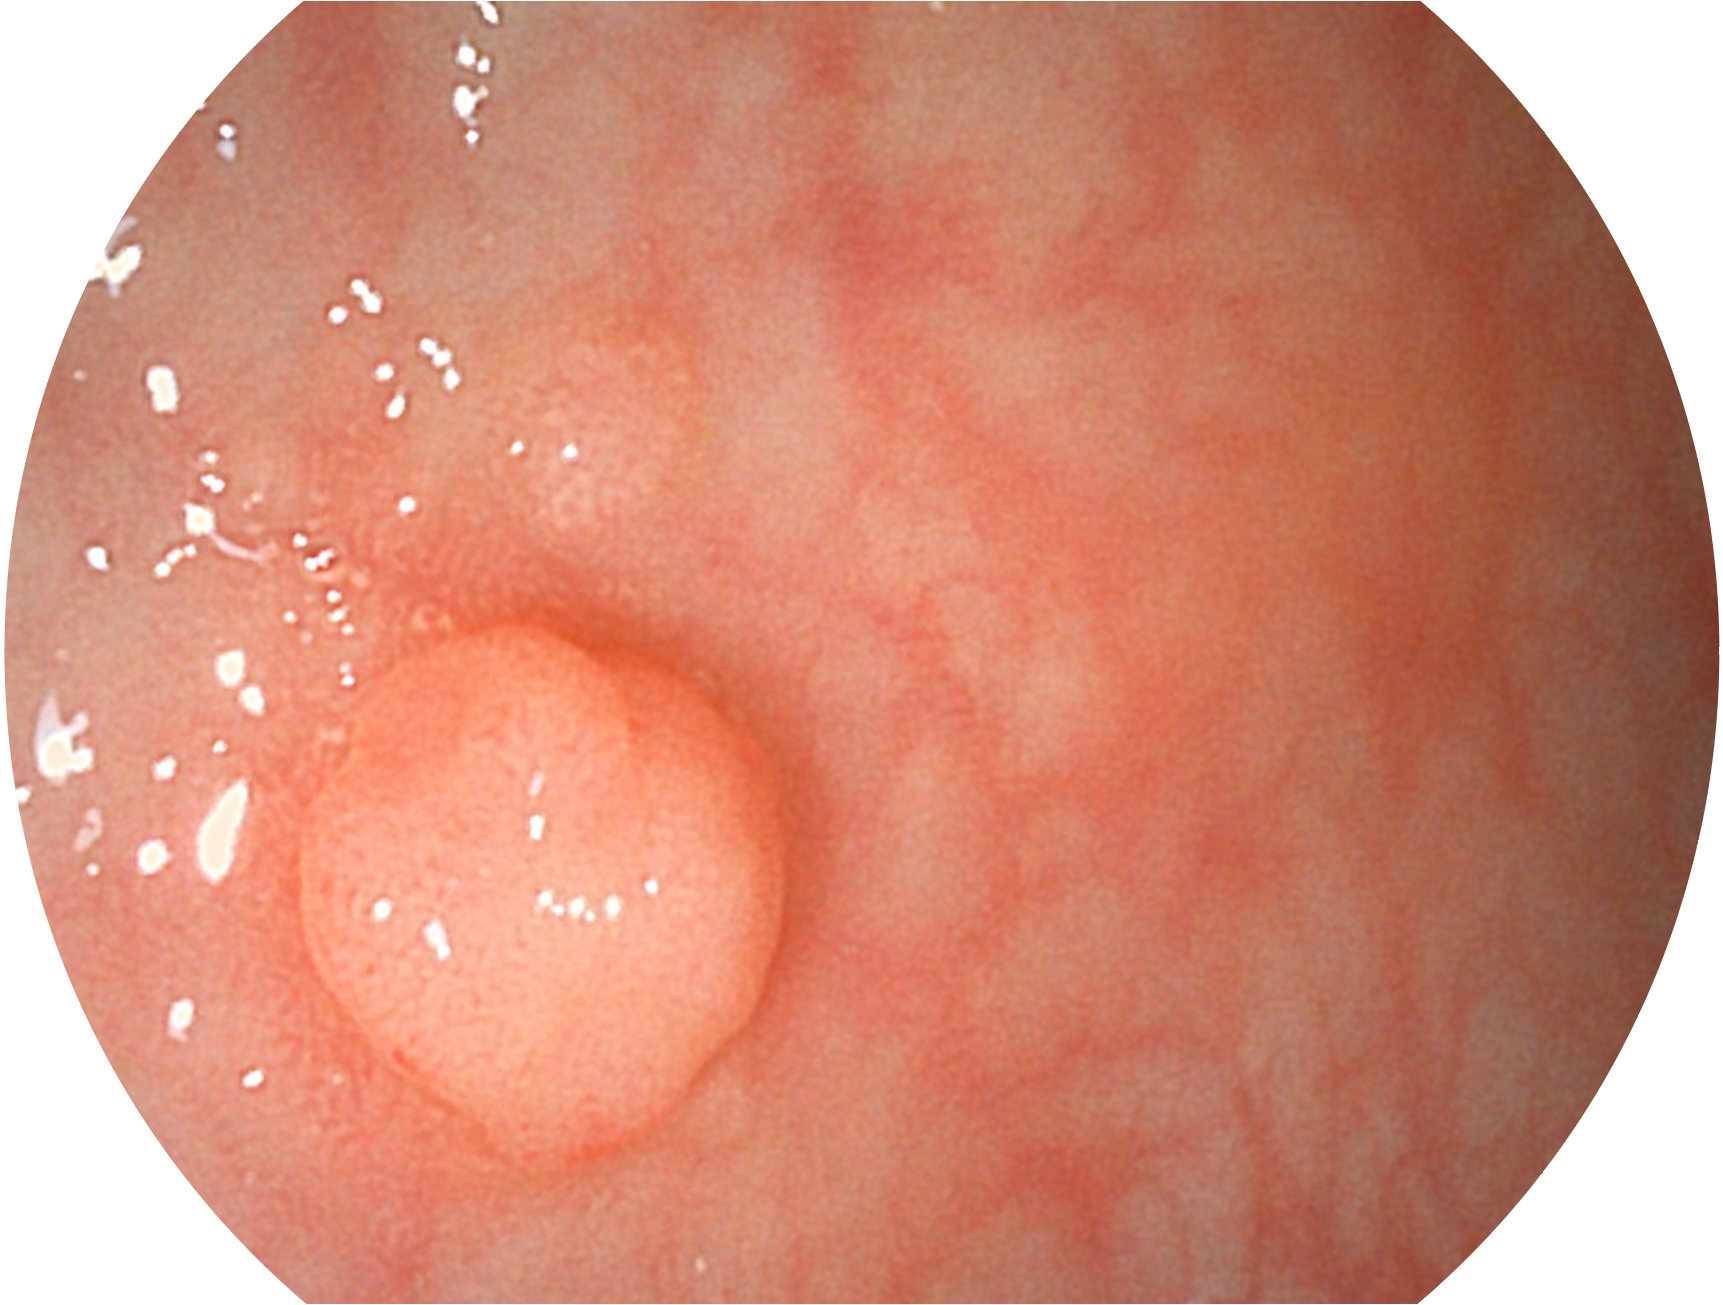

開立新開發(fā)的內(nèi)鏡染色技術(shù),主要是基于多波長LED 光源的開發(fā),VLS-55Q 四波長LED 光源是由四個不同顏色的LED光按照相應(yīng)照明模式所規(guī)定的特定發(fā)光比例進(jìn)行合束后形成,合束后形成的照明光的光譜由紅光、綠光、藍(lán)光及藍(lán)紫光這四個不同的波段范圍構(gòu)成。具有更高光譜自由度,通過光譜比例的控制,實現(xiàn)了聚譜成像技術(shù),英文全稱為“Spectral Focused Imaging, SFI”,縮寫為“SFI”和光電復(fù)合染色成像技術(shù),英文全稱為“Versatile Intelligent Staining Technology, VIST”,縮寫為“VIST”。